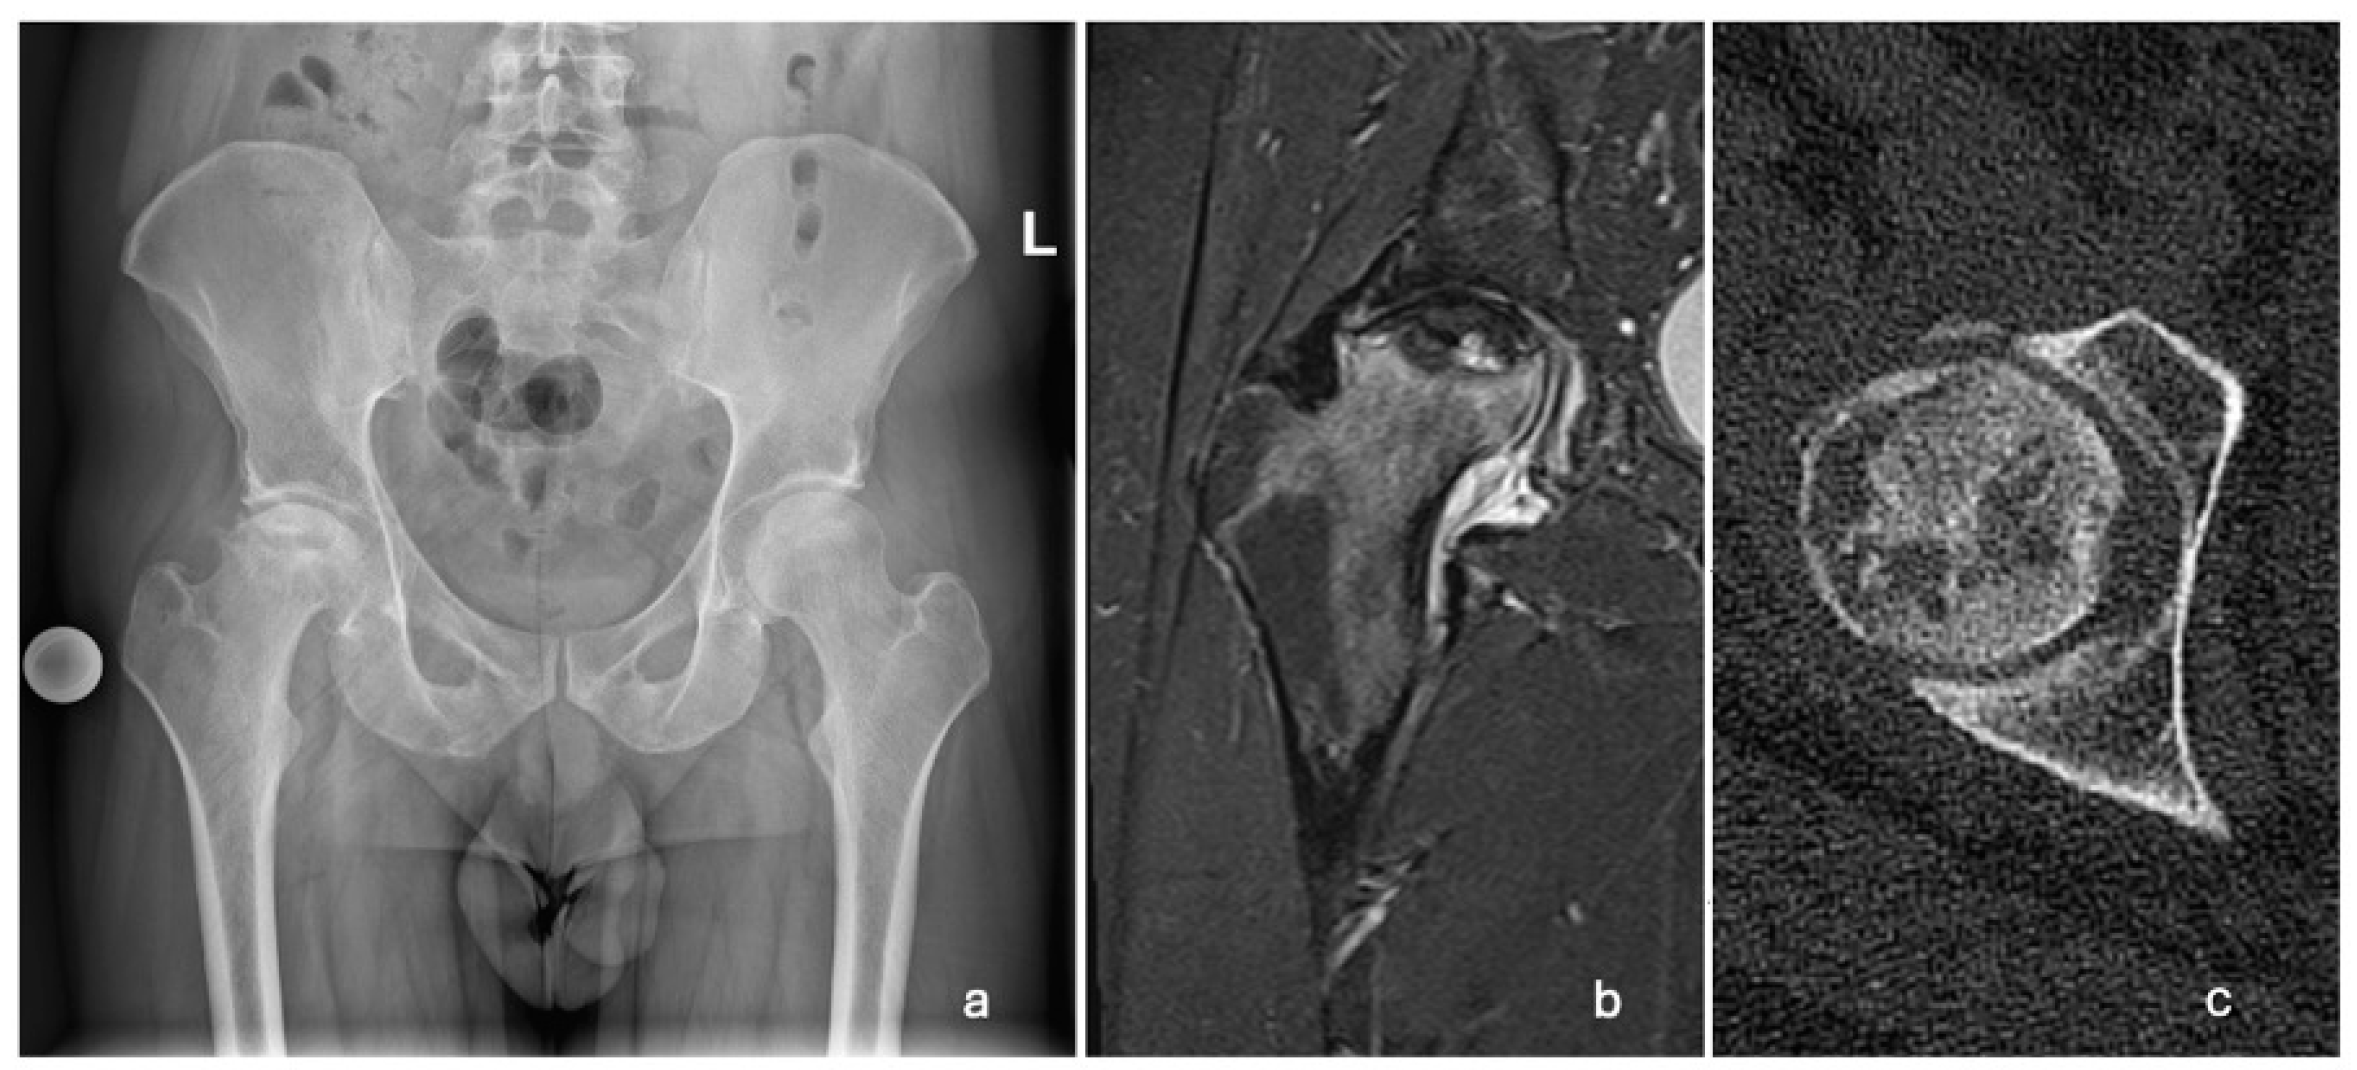

A 29-year-old Caucasian male patient presented to the emergency room in March 2022 with progressively increasing pain in his right hip over two months. Upon physical examination, the patient was limping and had extensively painful and limited rotations of the right hip joint. He was referred for an X-ray, a computed tomography (CT) scan, and magnetic resonance imaging (MRI) of the pelvis and both hips. The changes were indicative of stage 3 (Ficat and Arlet classification) ONFH of the right hip (Figure 1). The left femoral head was unaffected.

Figure 1.

Radiographic images showing unilateral ONFH of the right femoral head. (a) AP pelvis X-ray taken in March 2022, showing a Ficat and Arlet stage 3 right ONFH; (b) T2-weighted MRI of the right hip taken in April 2022, showing ONFH with a subchondral fracture and femoral head collapse >2 mm (Association Research Circulation Osseous stage 3B); (c) CT scan of the right hip showing cystic deformation, the loss of continuity, and the applanation of the anterolateral femoral head.